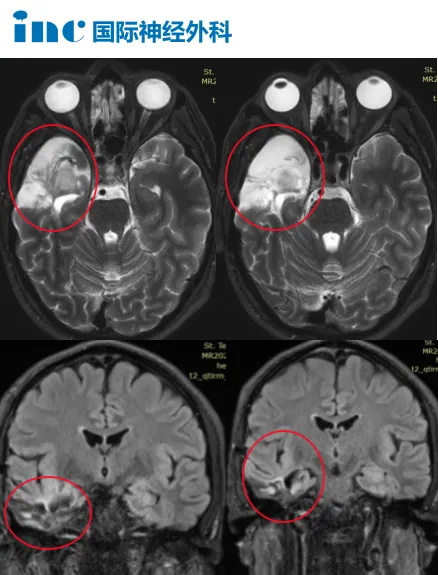

颞叶胶质瘤开颅术后3个月肿瘤复发,无法控制的癫痫

INC国际教授多次中国行,切实为海内外患者治疗带来更多选择。一名40岁法国颞叶弥漫性星形细胞瘤患者,因癫痫发作查出颞叶胶质瘤。一开始开颅手术后,术后3个月复发,癫痫也再次发作,且药物无法控制。香港的医生建议先尝试进行少量的替莫唑胺化疗,看看反应如何,然后再做另一次开颅手术。下一步该如何走?

等待对患者来说是不利的,因为这会给肿瘤继续生长的机会,手术应尽早进行,越早越好,因为那样我们就可以得到新的组织病理学结果,然后我们就会知道放疗和化疗是否有必要。肿瘤位于右侧颞叶区,我们可以进行很广泛的切除,甚至几乎超出肿瘤的边缘。

颞叶手术中,术中核磁也重要。在手术中,当你到达肿瘤和健康组织的边界时,它们看起来一样,无法区分,因为没有一个清晰的边界。当我们到达这个区域时,我们将停止手术,然后我们将把患者转移到术中核磁设备中,因为核磁成像仍然可以分辨出有多少残留肿瘤(还没切除的)。假设仍然有一厘米的肿瘤边缘,你用肉眼是看不到的,但你可以在核磁成像中看到,然后我们就知道还可以顺利切除多少。通过术中核磁,我们可以比仅使用显微镜更能精确地切除肿瘤。